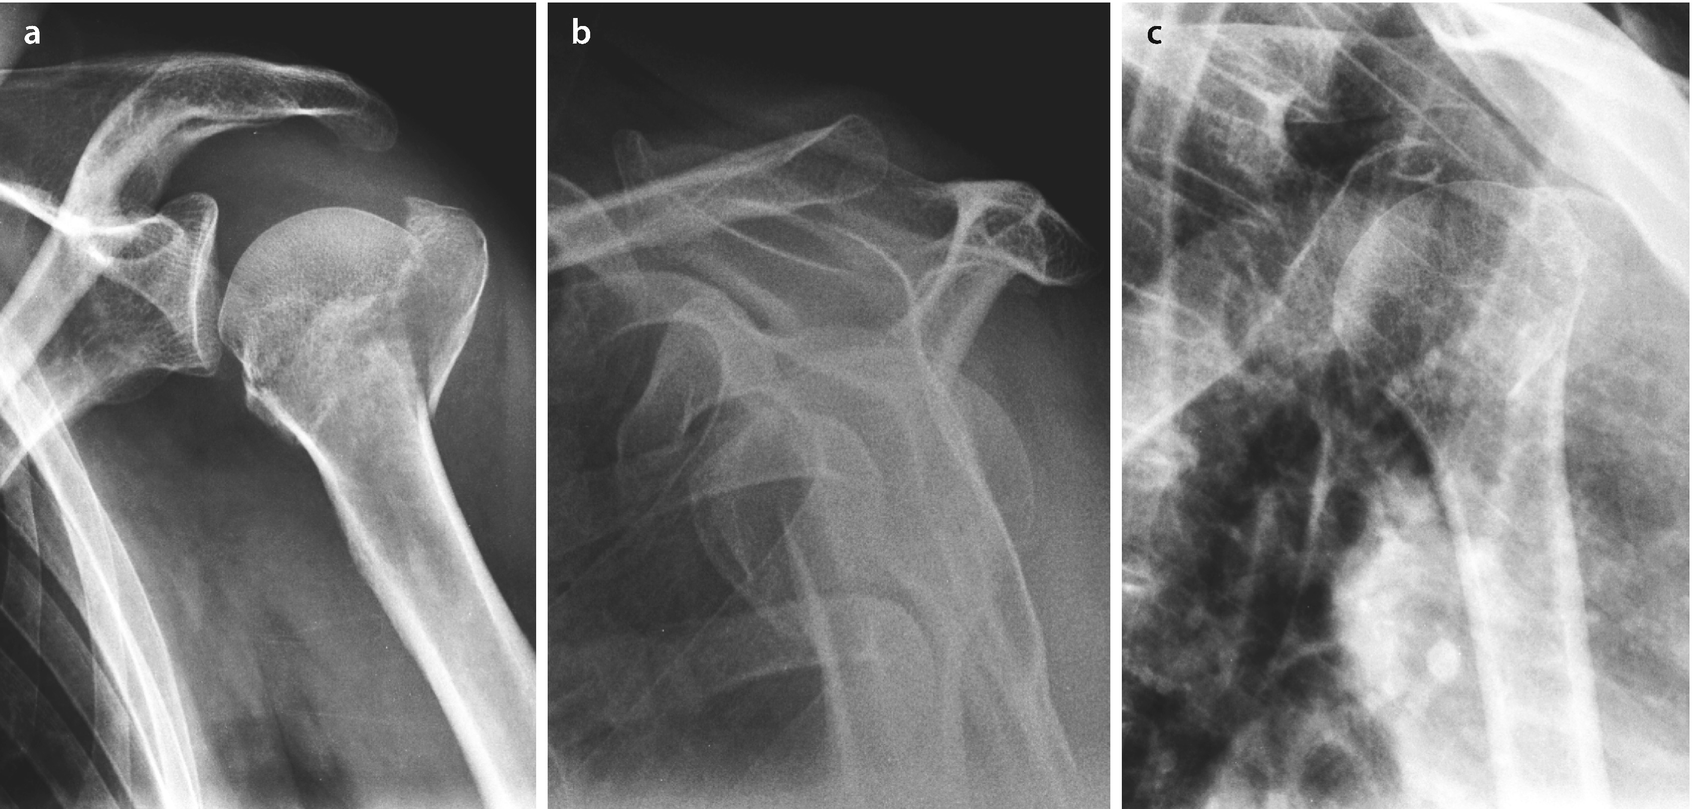

Auch die valgisch impaktierte Fraktur stellt eine gute Indikation für eine konservative Therapie dar. Bei einer Tuberculum majus-Fraktur bei der die Bruchstücke verschoben sind ist oft zusätzlich das Schultergelenk verrenkt. Skapulafraktur Incisura-scapulae-Syndrom Definition.

Luxationsfraktur von oberem Sprunggelenk Hüftgelenk. Bei einer Fraktur Knochenbruch ist die Kontinuität des Knochens komplett oder teilweise unterbrochen. Bei der seltenen Skapulafraktur handelt es sich um eine Fraktur des Schulterblattes bei der man insbesondere zwischen intraartikulären Frakturen mit Beteiligung des Glenoids und extraartikulären Frakturen unterscheidet.

Nach inadäquatem Trauma aufgrund einer erkrankungsbedingten Schwächung des Knochens entsteht. Die fur die Prognose einer Femurkopfnekrose angeblich rele-. Dargestellt ist der Oberarm in voller Länge mit Abbildung der Schulter sowie des Ellenbogens.

Die Abbildung unten zeigt ein Röntgenbild des gesamten Oberarms. Fraktur von 3 benachbarten Rippen. Die häufigste Weber A Fraktur ist die vom Typ A.

Valgus Impaktierte 3 Fragment Fraktur Humeruskopf Links Springerlink